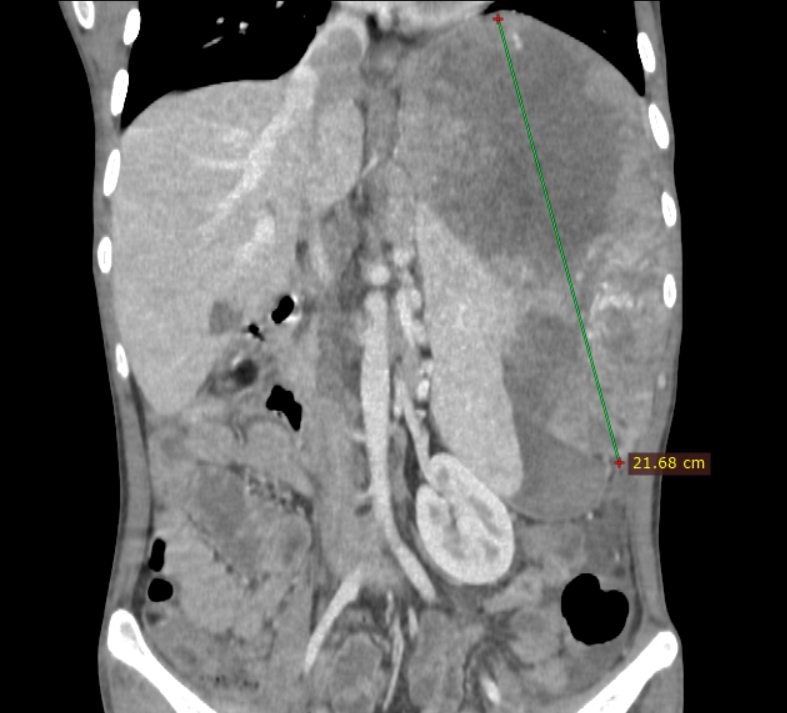

Hình ảnh khối u gan kích thước lớn của bệnh nhân 26 tuổi. Ảnh: BSCC.

Kể lại với Tri Thức - Znews, bác sĩ chuyên khoa II Nguyễn Trường Giang, Phó giám đốc Trung tâm Phẫu thuật Gan mật - Tiêu hóa - Bệnh viện Bệnh Nhiệt đới Trung ương, cho biết tiếp nhận bệnh nhân trong tình trạng ốm yếu, chỉ nặng có 40 kg vì đau không ăn uống được và nhiều ngày dùng thuốc không rõ nguồn gốc, khối u gan đường kính hơn 20 cm, xâm lấn tĩnh mạch chủ dưới, đã vỡ gây chảy máu ồ ạt.